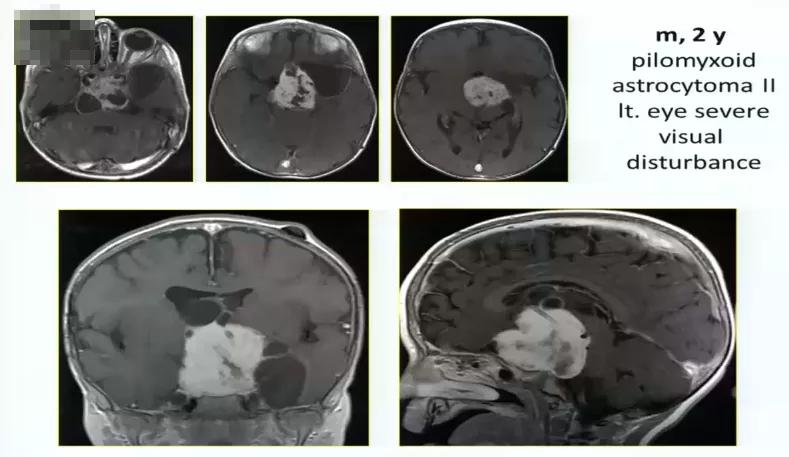

视路胶质瘤全切手术病例2:

2岁男孩,毛状黏液样星形细胞瘤2级,严重的左侧视觉障碍,肿瘤巨大

术中情况: 采取眶颧入路,肿瘤非常大,累及向上向下,需要宽广的视野。

术后情况: 肿瘤全切,术后一年,孩子状态良好。小儿肿瘤放化疗专家为其进行后续治疗。